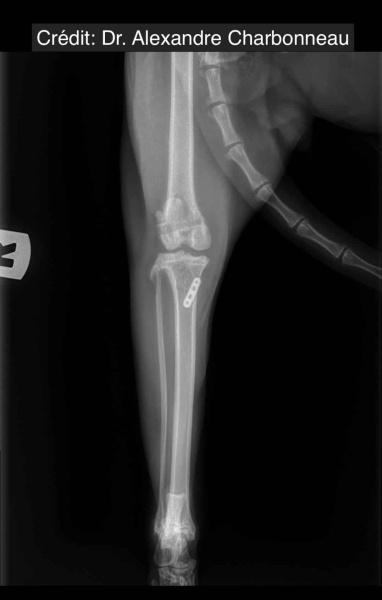

Radiologické snímky

NOVALIG® je syntetický vaz, který lze použít k rekonstrukci vazů a rychlému obnovení jejich fyziologických funkcí.

V případě zkřížených vazů umožňuje intraartikulární rekonstrukci v izometrických bodech připojení, čímž obnovuje biomechaniku kolene a všechny funkce natrženého vazu.

V případě více vazů kolene (kraniální, kaudální, kolaterální) je možné pomocí NOVALIG® anatomicky rekonstruovat každý vaz.